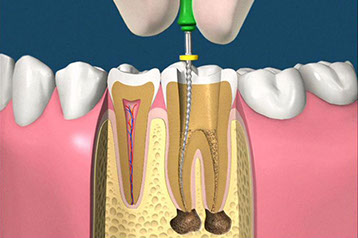

• accesso alla camera pulpare mediante frese diamantate

• asportazione della polpa e sagomatura dello spazio endodontico con strumenti meccanici (in nichel-titanio), con l'ausilio della detersione del canale radicolare (acqua ossigenata, ipoclorito di Sodio, calcio-chelanti)

• otturazione di tutto l'endodonto mediante materiali termoplastici (guttaperca) e cementi biocompatibili

• controllo radiografico